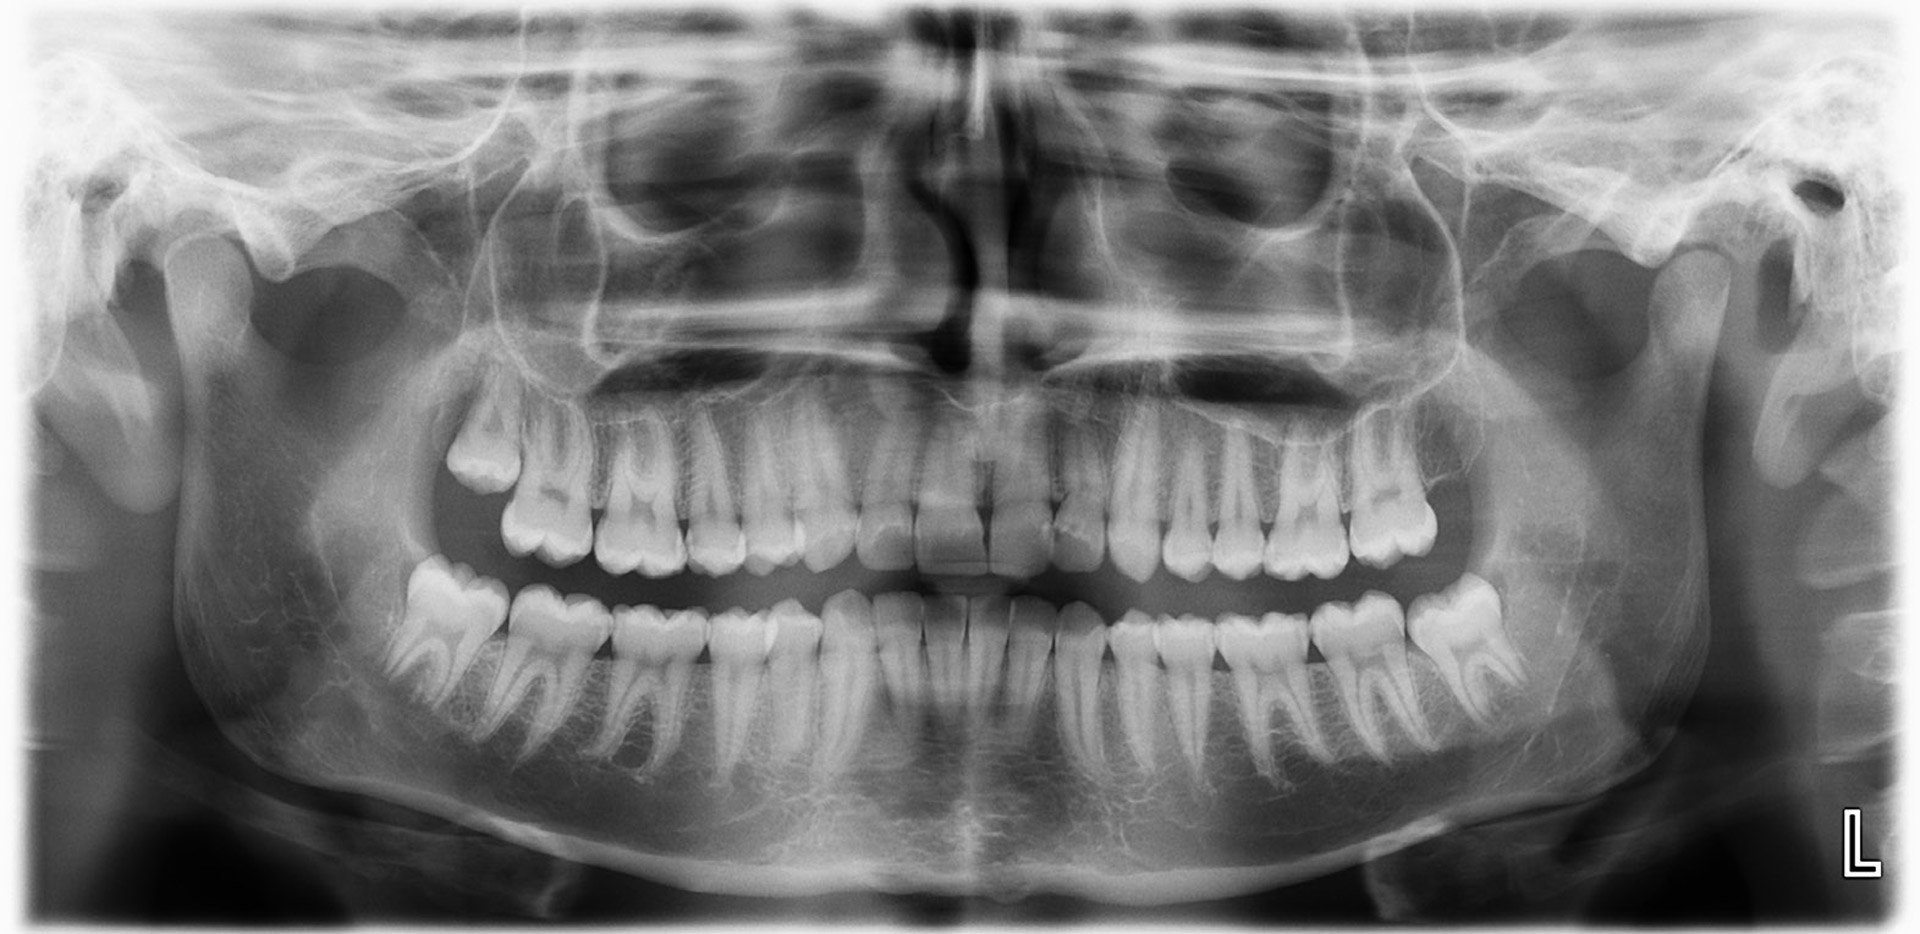

Nordisk tema: Rettsodontologi Age estimation by means of teeth Age estimation in children is applied in the identification process of a deceased child or when the age the child is questioned. In young individuals tooth development on radiographs as well as eruption are inspected, In adults several degenerative changes can be evaluated either in the laboratory or radiologically. From a deceased individual tooth specimens can be extracted for age estimation purposes which is obviously not possible for the living. Age estimation methods by means of the teeth are reviewed. Les artikkel

Nordisk tema: Rettsodontologi Minor or adult? A different approach in the Nordic countries vs Europe Around 1 out of 5, or 150 million children under the age of 5 worldwide are unregistered or lack a birth certificate. Unaccompanied minor migrants have many benefits, inaccessible to adults. It is evident that the age of migrants is one of the key variables that must be ascertained. Equally, it is important that juveniles are housed under safe conditions, including not with adults stating to be children. Les artikkel

Nordisk tema: Rettsodontologi Retsodontologisk identifikation Tandvæv og tandrestaureringer kan modstå ekstreme påvirkninger. Ved odontologisk identifikation sammenligner man præcise og detaljerede odontologiske registreringer på afdøde individer med journaloplysninger fra savnede personer. Retsodontologisk identifikation og profilering er typiske opgaver for retsodontologer. Odontologisk identifikation kan være essentiel, når uidentificerede lig bliver fundet, og relevant såvel i enkeltsager som efter massekatastrofer, når ligene er nedbrudt til ukendelighed eller groft mutilerede, eller hvis der kun foreligger skeletrester. Retsodontologisk identifikation anerkendes internationalt som en af de tre såkaldte «primære identifikationsmetoder» – sammen med fingeraftryk og DNA. Les artikkel